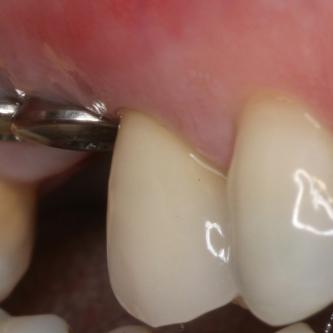

Exemple 3: Un implant à la place d'une incisive latérale supérieure droite. Sur cette image on voit le moignon en titane qui est vissé sur l'implant.

Exemple 3: Puis sur ce moignon, la couronne en céramique est scellée.

Exemple3: La couronne en place.